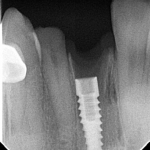

RADIOGRAFICAS PERIAPICALES Herramienta esencial para identificar implantes dentales LA CLAVE PARA IDENTIFICAR IMPLANTES. La identificación de implantes dentales sin información previa es una situación frecuente...

RADIOGRAFICAS PERIAPICALES Herramienta esencial para identificar implantes dentales LA CLAVE PARA IDENTIFICAR IMPLANTES. La identificación de implantes dentales sin información...